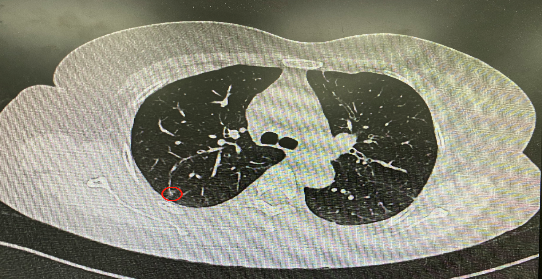

今年54歲的李女士(化名)7月初突然出現(xiàn)右上部腹痛,起初并未在意,以為稍作休息就會好轉(zhuǎn),但疼痛卻并未消退,持續(xù)了一個(gè)星期。李女士實(shí)在難以忍受,才在家人陪伴下來到西安國際醫(yī)學(xué)中心醫(yī)院就診。胸外科二病區(qū)崔凱主任接診患者后,詳細(xì)詢問病情并查閱檢查資料,經(jīng)胸部HRCT檢查,結(jié)果提示:右肺上葉后段混合密度結(jié)節(jié)影,考慮原位癌可能,即將患者收入胸腔外科二病區(qū)住院治療。

經(jīng)與患者家屬溝通,崔凱主任決定行外科手術(shù)治療。為達(dá)到精準(zhǔn)切除,術(shù)前需進(jìn)行肺小結(jié)節(jié)切除前定位。由于結(jié)節(jié)位于右肺上葉后段,傳統(tǒng)經(jīng)胸外穿刺術(shù)無法抵達(dá)病灶。崔凱主任與呼吸內(nèi)科一病區(qū)歐陽海峰主任討論后,決定擬行LungPro全肺診療導(dǎo)航下染色定位。即術(shù)前通過Lung Pro導(dǎo)航規(guī)劃染色位置,經(jīng)Lung Pro實(shí)時(shí)引導(dǎo)支氣管鏡抵達(dá)既定位置,注入亞甲藍(lán)染色劑標(biāo)記結(jié)節(jié)位置。

使用術(shù)前規(guī)劃系統(tǒng)重建全肺3D模型,并于外科醫(yī)生討論染色位置,最終確定標(biāo)記染色點(diǎn)—右肺上葉后段b亞段(RB2b)。術(shù)中使用P290(4.9mm外徑)標(biāo)準(zhǔn)支氣管鏡,根據(jù)導(dǎo)航術(shù)前規(guī)劃路徑,Lung Pro實(shí)時(shí)導(dǎo)航下,GS鞘管進(jìn)入RB2b遠(yuǎn)端官腔外病灶并注射亞甲藍(lán)染色劑。